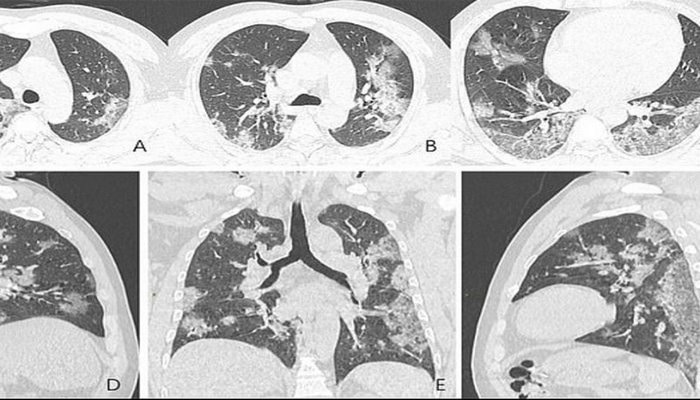

Koronavirüsten ölen 44 yaşındaki Çinli bir erkeğin röntgen filmleri ve bilgisayarlı tomografisi yayınlandı. Hastalığın insanların akciğerlerine ne yaptığını açıkça gösterir. Taramalarda, akciğerlerde beyaz lekeler görülebilir, bunu da radyologlar “buzlu cam” türü olaraq bilinen subplevral odak deyisiklikleri kimi gosterirler. Koronavirüs kurbanlarındaki doktorlar tarafından belirlenen benzer deyişiklikler atipik pnömoni (Zatürre) ve Orta Doğu solunum sendromunda bulunanlara benzer.

Bu, Wuhan'daki deniz ürünleri pazarında çalışan ve koronavirüsdan ölen adamın göğsünün röntgeni. Tam da orada salgın başlamıştı. Anormallikleri açıkça gösteriyorlar. Taramalar Kuzey Amerika Radyoloji Topluluğu tarafından sunulmaktadır. Taramalarda erkeğin akciğerlerinin boşluklarındaki sıvının zamanla nasıl daha belirgin hale geldiğini gösteriliyor. Hasta, geçen yıl yaklaşık iki hafta boyunca ateş ve öksürük şikayetlerinden sonra 25 aralıkta hastaneye kaldırıldı. Hastaya pnömoni ve akut solunum sıkıntısı sendromu teşhisi kondu.

Doktorlar ona gerekli tüm yardımı sağladı, ancak buna rağmen bir hafta sonra öldü. Wuhan şehrini ziyaret ettikten sonra koronavirüsa yolukmuş 54 yaşındaki kadının taramaları da, akciğer boşluğunun kısmi sıvı ile dolmasını gösterdi. Kadına, bir hafta süren ateş, öksürük, yorgunluk ve göğüsteki durgunluk belirtileri sonrası virüsün neden olduğu şiddetli pnömoni teşhisi kondu.Daily Mail hastaya oksijen ve antibiyotik tedavisi edildiyini yazıyor.